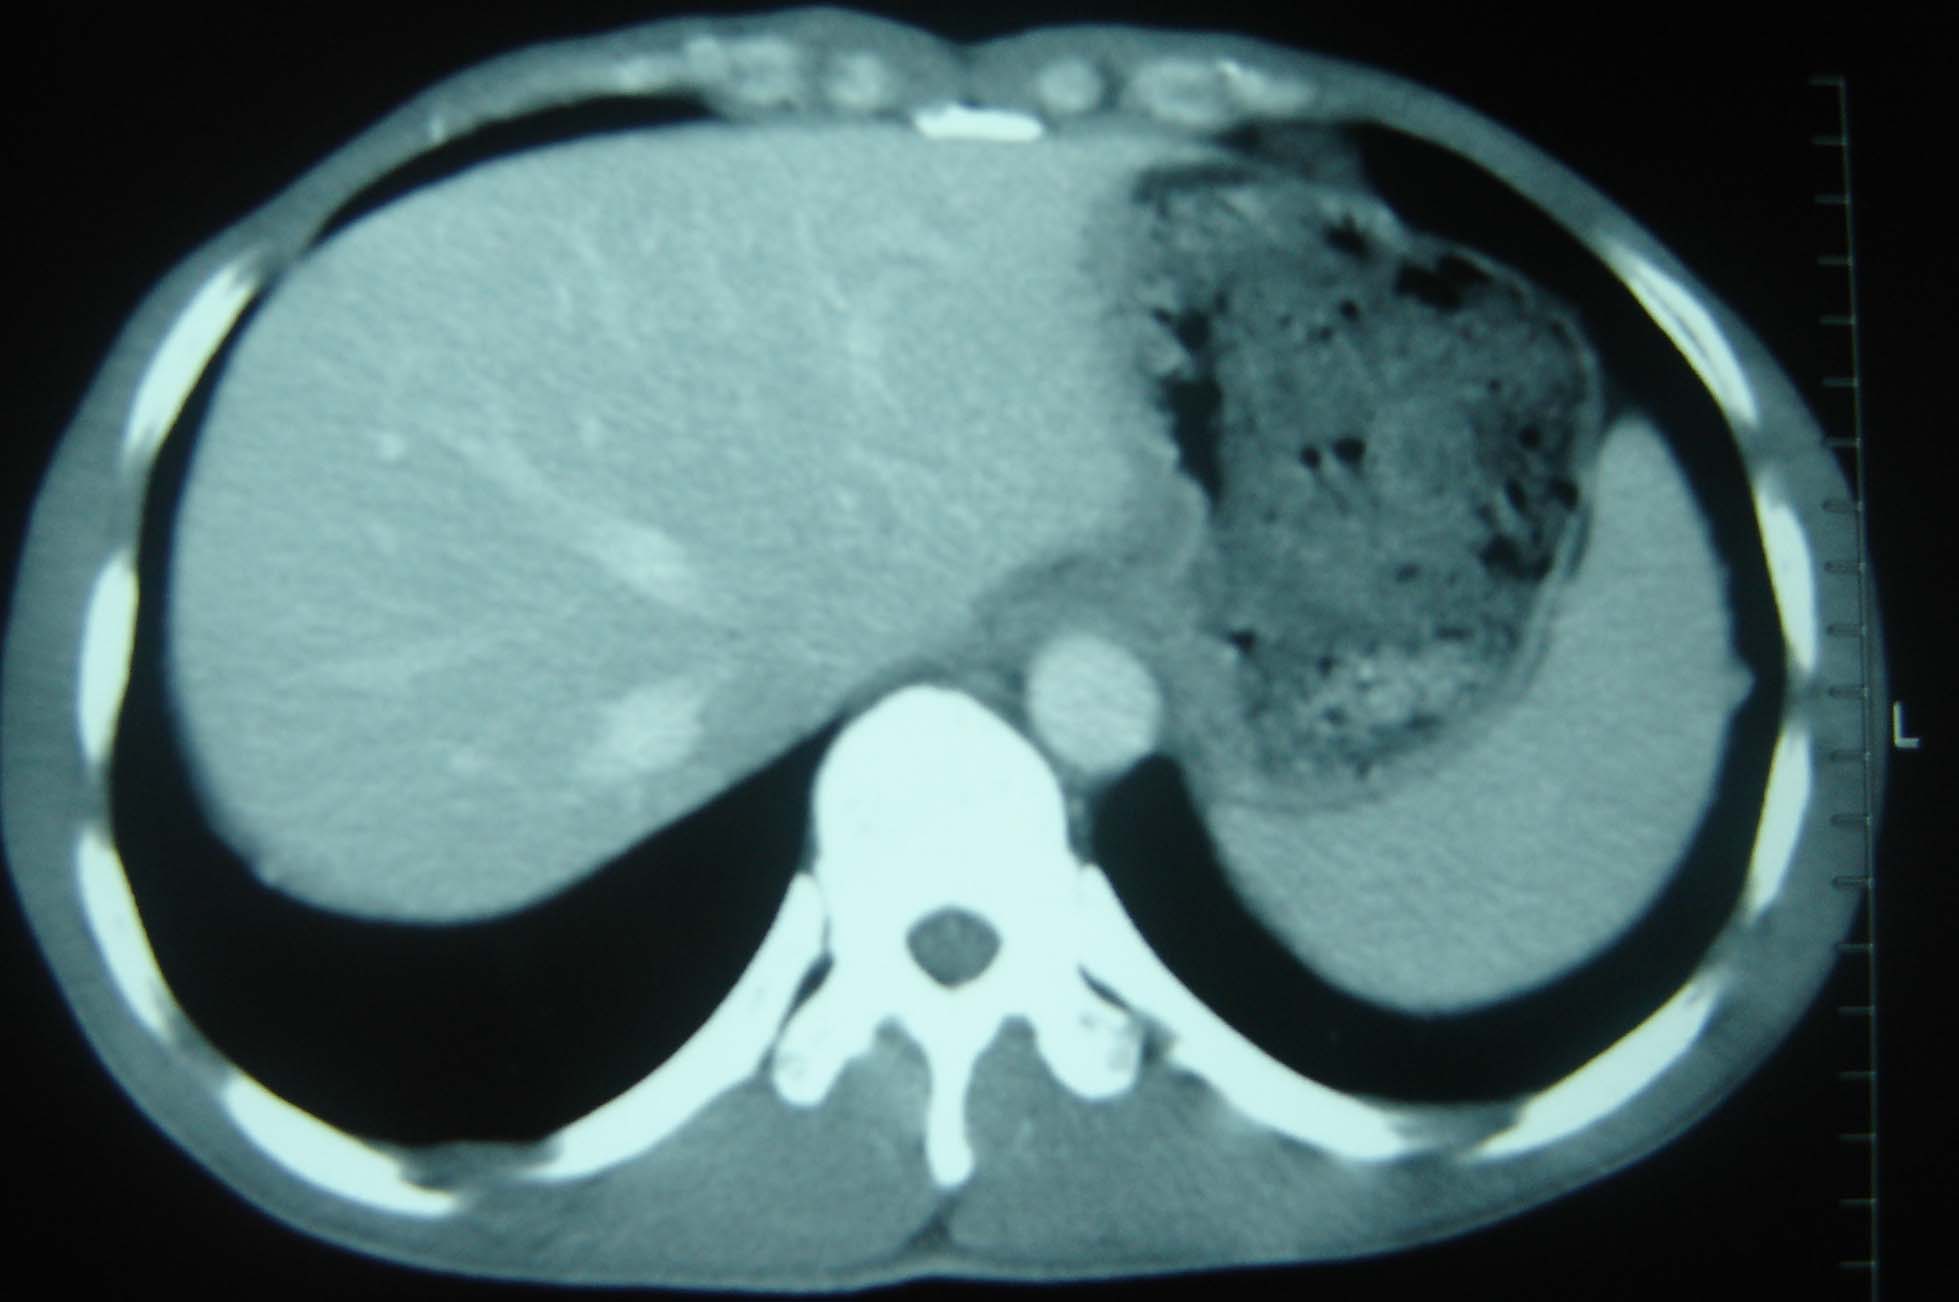

男 、43岁,咳嗽胸痛,装修工,平时接触粉尘较多,有吸烟史10多年,纤维支气管镜检查未发现异常,胃镜、腹部b超检查亦未发现异常,颈部淋巴结活检未发现肿瘤细胞。

1)考虑双肺及胸膜多发性转移瘤。2)肺气肿。